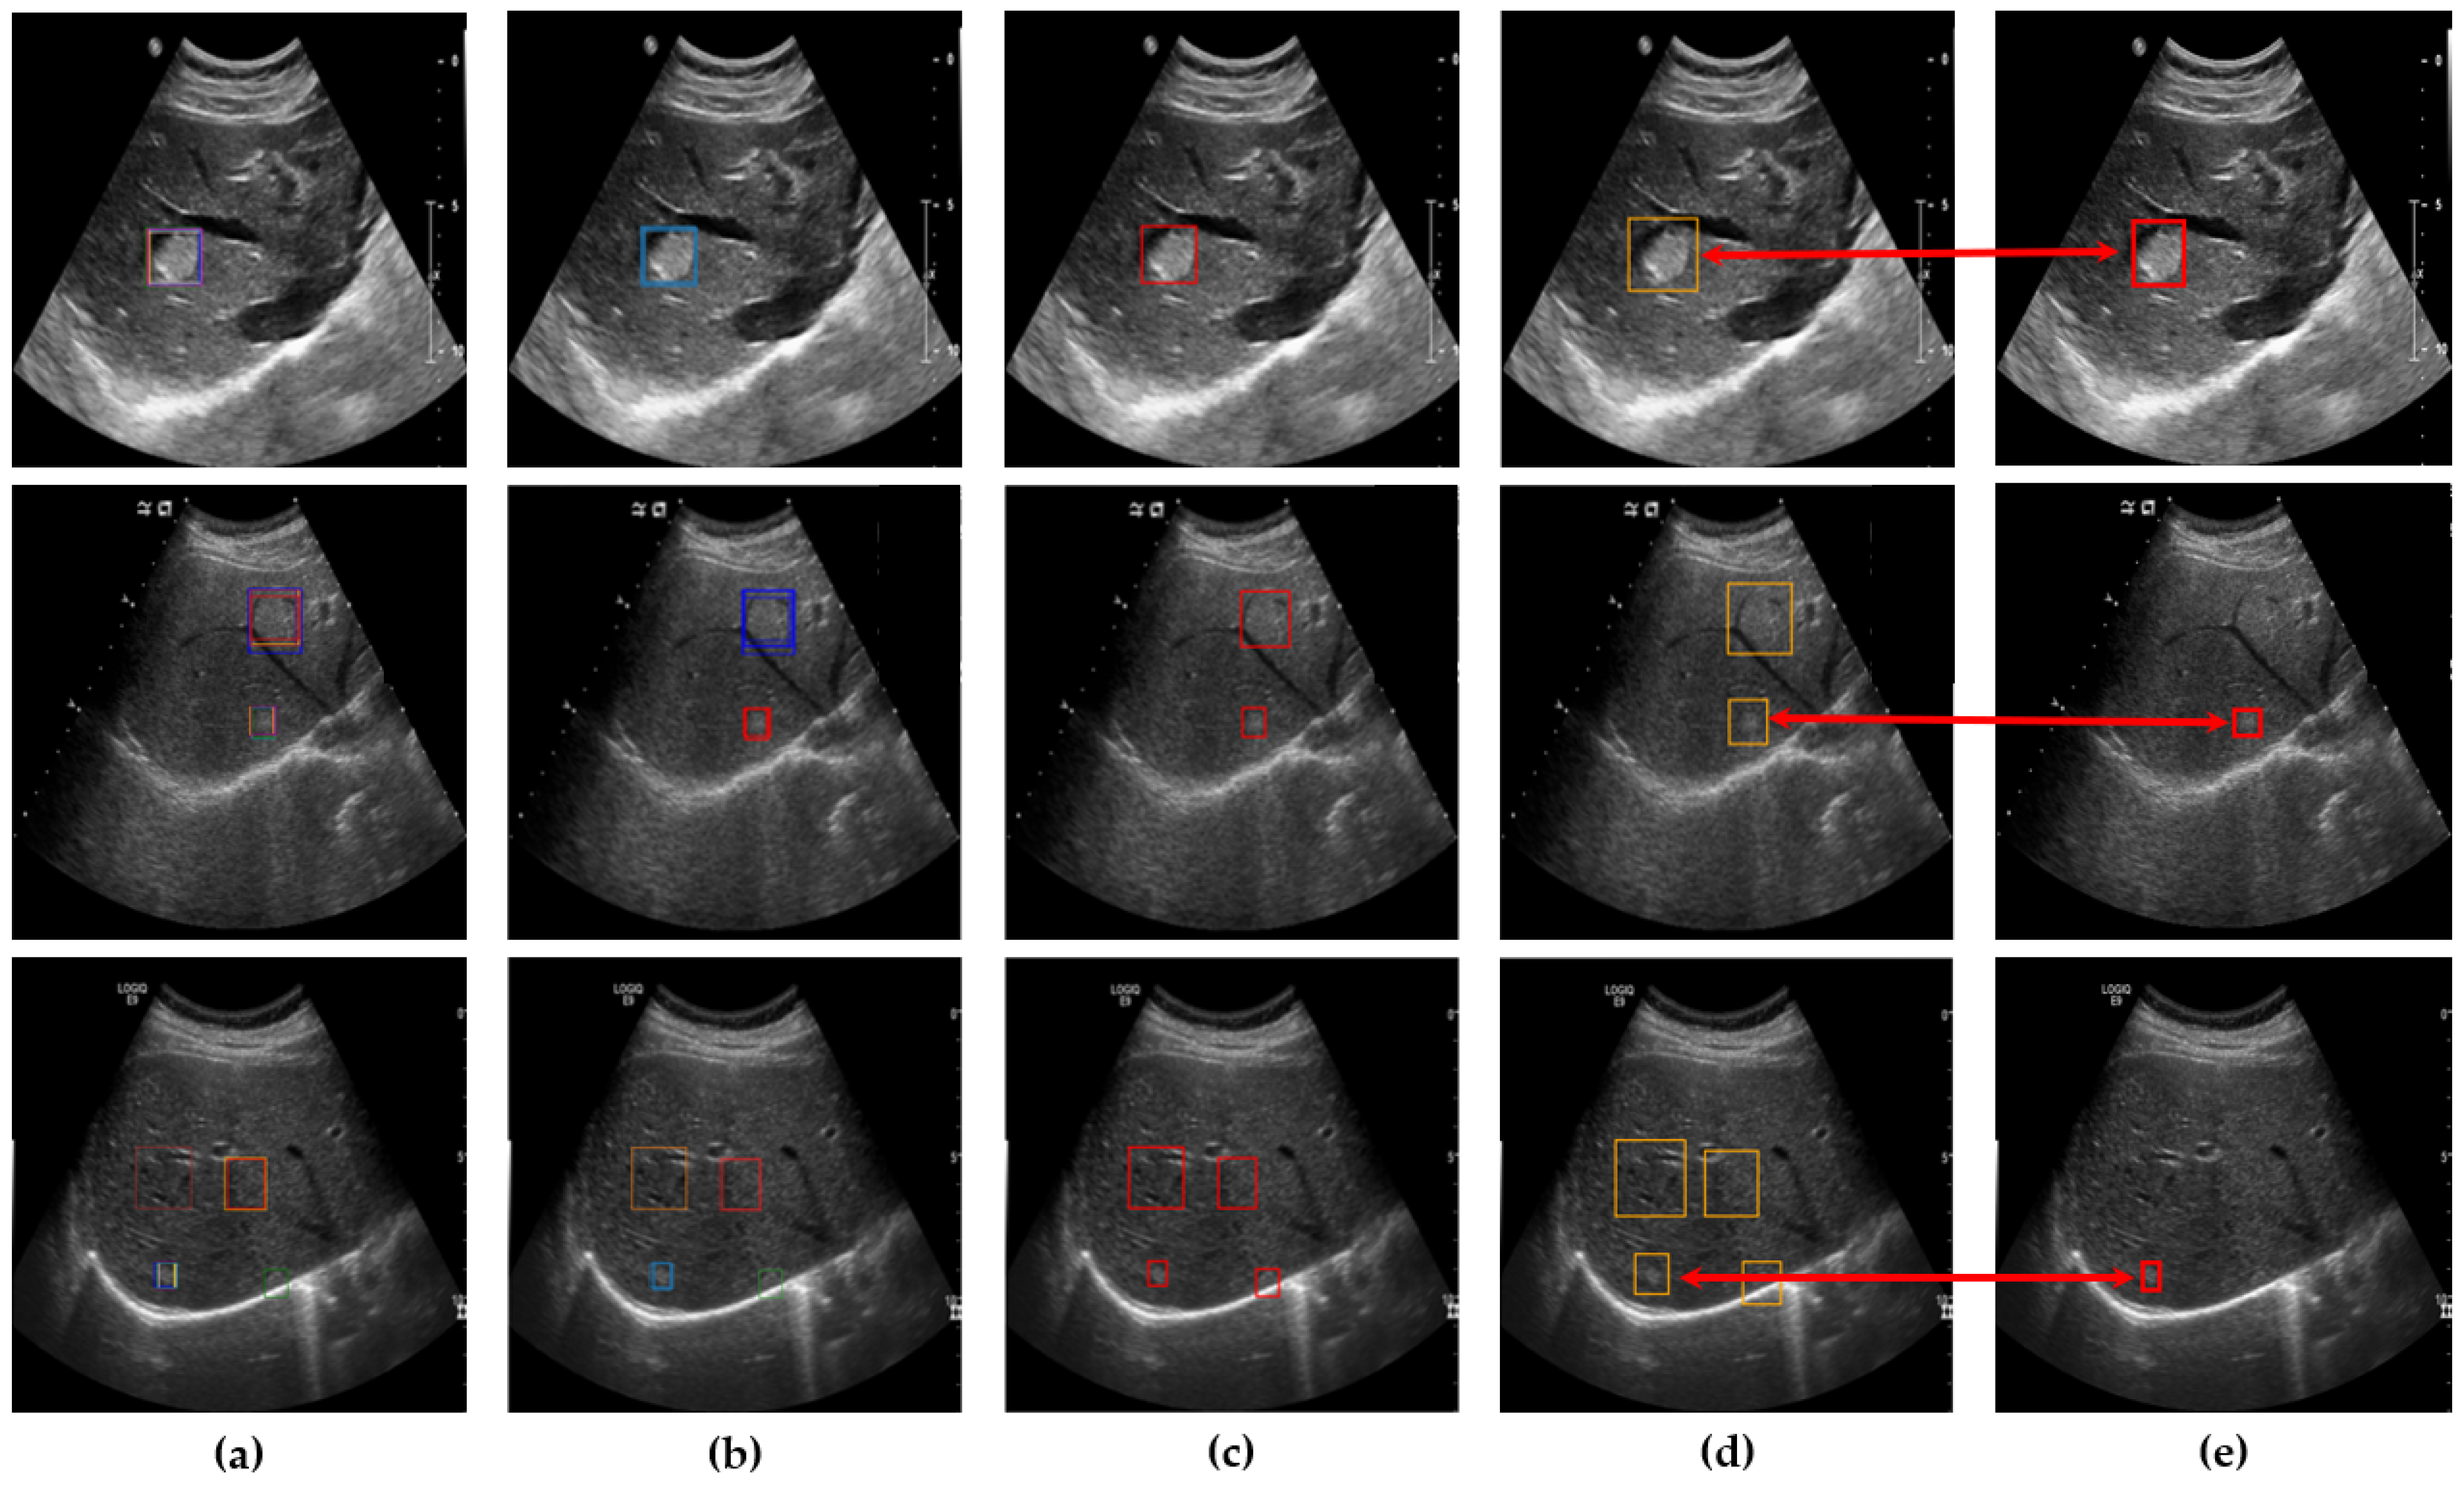

Since ultrasound imaging is frequently used for real-time diagnostics, fast lesion detection is crucial. YOLOv8 offers a more lightweight architecture and optimized computation compared to YOLOv5, enabling faster inference speed. For this reason, we chose YOLOv8 for our approach. As illustrated in Figure 4, we employed YOLOv8 to develop the lesion detector and trained a total of ten networks using ten different datasets. A low threshold was applied during the detection process to generate a larger number of bounding boxes. While a higher threshold might improve accuracy metrics, it often results in missing smaller lesions, particularly those in early stages, or lesions that deviate significantly from the average size. Such omissions would render the system less effective in clinical applications, despite high accuracy metrics. By applying a lower threshold, each network produced between zero and five bounding boxes, which were then utilized in the subsequent steps.

Figure 4.

Lesion suspected regions, green bounding box, detected by YOLOv8.

After clustering and outlier reduction, SM-WBF was applied to generate a single representative bounding box for each cluster. SM-WBF calculated weights for each bounding box by normalizing the mAP@0.5 values of the ten networks using the SoftMax function. These SoftMax weights were then used to combine the center coordinates and dimensions of the bounding boxes within each cluster through a weighted average approach. This method ensured that bounding boxes from higher-performing networks contributed more significantly to the result. Details of this process are illustrated in Figure 7.

Figure 7.

(a) An image with all bounding boxes detected by YOLOv8 overlaid, and the results of bounding box optimization through (b) clustering, (c) SM-WBF, and (d) padding. (e) Ground truth bounding box.

Table 1 compares the results across four different scenarios, presenting mAP@0.5 scores, the number of correctly detected lesions in the test data, and the resulting accuracy. When a single YOLOv8 model was applied to the original US images without any preprocessing, the mAP@0.5 was 0.6128, and the model detected 101 lesions out of 180 test cases, achieving an accuracy of 56.11%. After applying our preprocessing steps to generate ten networks, clustering the bounding boxes, and performing SM-WBF, the method detected 172 out of 180 test cases, with an accuracy of 95.56%. In our evaluation using 180 test images, we compared the detection performance of YOLOv5, YOLOv8, and YOLOv11. YOLOv5 detected 167 lesions, YOLOv8 detected 172 lesions, and YOLOv11 detected 171 lesions, demonstrating that YOLOv8 achieved the best detection performance. It is important to note that YOLO has many versions, and the most suitable version varies depending on the dataset. The accuracy values presented here are not generalizable but are specific to our dataset.

Although the mAP@0.5 score was relatively low, this was because the clustering process preserved all potential bounding box regions, ensuring comprehensive lesion detection. However, the primary focus of our method is not achieving a higher mAP@0.5 but maximizing the capability to detect actual lesions, which demonstrates its performance was outstanding.

The bounding box optimization process contributed to enhancing the reliability and quality of the detection results by eliminating redundancies through clustering, refining outliers, and applying padding. The final bounding boxes encompassed the tumor contours without loss, providing a stable input for lesion classification models. This significantly improved the accuracy of the diagnostic support system.